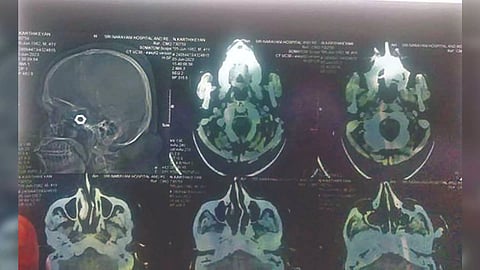

Karthikeyan’s relatives, who were not satisfied with the treatment at the GH, took him to a private clinic, and were shocked as the X-ray done at the private clinic showed the presence of a nut in the skull. The doctors allegedly sutured the wound without removing the foreign object.